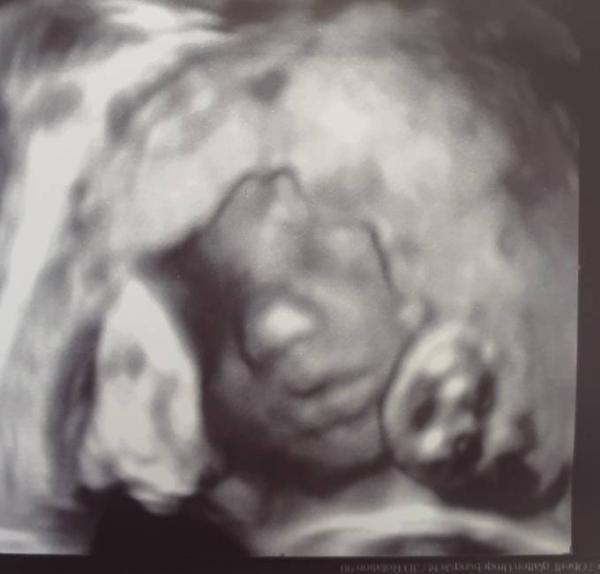

Also, ich hatte gestern wieder einen Termin und habe jetzt 10kg zugenommen. Ich muss ehrlich sagen das ich sehr sehr viel esse Bei meiner ersten Schwangerschaft habe ich mich mehrfach täglich von Anfang bis Ende übergeben müssen und habe ebenfalls 10kg zugenommen Habe übrigens zwei super süße Bilder bekommen Wünsche euch allen einen tollen Tag

Bild zu